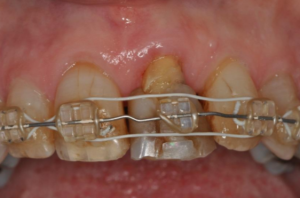

Tom calls this ‘your shop front’. I agree with him – he’s right that appearance and smile are so important. In this case, the gap was larger than the adjacent central incisor. However, the patient was keener on filling the entire space rather than having some form of diastema. Giving all patients the full options including orthodontics, at any ages, is something that has to be considered. After six months of orthodontic extrusion treatment, this patient had formed new bone with a better smile line but what was needed next was a new tooth. This is where Dr. Tom’s expertise came in with implants.

Leaving the wires and brackets in place on all the other teeth, the central incisor was carefully removed and the small socket cleaned of any debris. There was still a residual bony defect but it was mainly width – so the implant was placed using bone graft Bio-Oss covered with a Bio-Gide membrane to add further width to the site. The flap was released, to give full coverage of the site and to allow the Implant and graft to integrate. The crown of the tooth was removed from the root, the defect within the tooth was sealed with a flowable composite and this allowed the crown of the tooth to be retained by the orthodontic wires acting as a temporary tooth.

This arrangement allowed the patient to have a temporary smile during the healing process. The implant was left for four months before uncovering and loading. This lady had had a darker tooth for such a long time that she wanted her crown to be slightly darker than the other teeth, so this was taken into consideration when shading up to her natural teeth. The crown was made to fill the gap, fortunately, the patient was quite happy with this. The original plan and positioning of the implant were to use a screw-retained bonded crown to allow flexibility in adapting her gum line and a degree of retrievability.